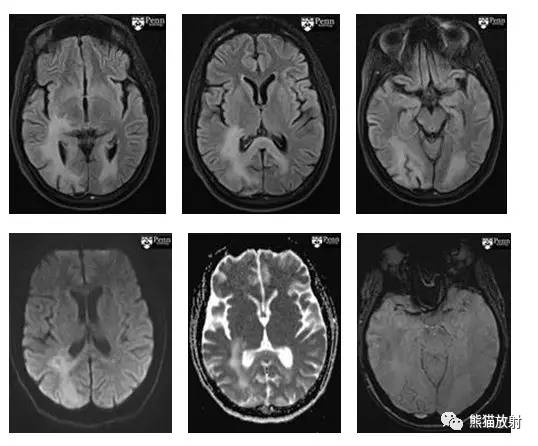

CASE 3

病史:患者女性,32 岁,因精神紊乱改变入院。

MR 图像依次为:液体恢复反转图像(FLAIR, 前三幅),弥散加权图像(DWI)、表观弥散系数图(ADC 图)和磁敏感加权图(SWI)。

影像表现

CT:在双侧顶叶、枕叶皮层下白质、深部白质束和胼胝体可见多发融合的密度减低区。无占位效应,灰质密度未见明显异常。

MRI:双侧顶枕叶皮层下白质、深部白质和胼胝体区见异常 FLAIR 信号。DWI 未见弥散受限。

诊断:结合临床病史,以上影像学表现符合进行性多灶性白质脑病(PML)